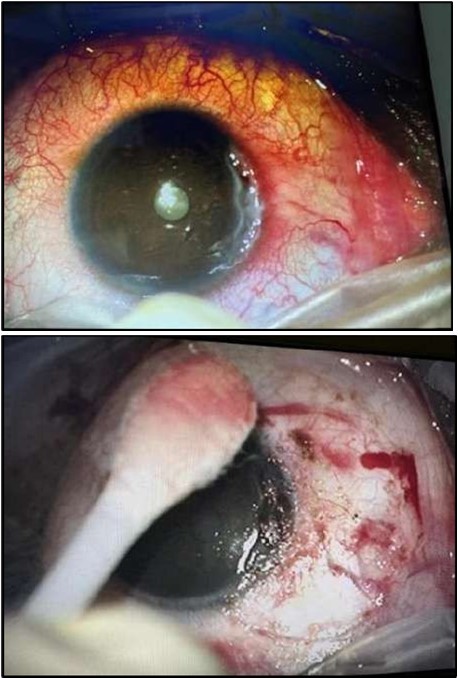

Two weeks post-surgery, the left eye showed significant healing, with a small conjunctival granuloma and vascularization at the ulcer margins. The cornea was clear with a central leading edge nasally, deep and quiet anterior chamber and clear lens. VA 6/6 bilaterally and IOP normal. Histopathology of excised conjunctiva showed non-keratinized squamous epithelium with superficial erosions, stromal elastosis, hemorrhage, and inflammatory infiltration, but no signs of granulomatous disease, malignancy, or viral evidence, findings consistent with idiopathic localized inflammatory process. The patient reported significant relief and satisfaction post-surgery, resuming normal activities. Treatment continued with oral prednisolone 25 milligrams every other day, tobramycin-dexamethasone ointment twice daily, and preservative-free artificial tears four times daily Figure 4, Figure 5a, Figure 5b, Figure 5c, Figure 5d.

Figure 4.OS. Slit-lamp photograph showing a partially quiet ocular surface two weeks following surgical excision of adjacent perilimbal conjunctiva.

Figure 5a.OS, Hematoxylin and eosin (H&E) stained section of the corneal specimen demonstrating full-thickness epithelial loss with underlying stromal necrosis.

Figure 5b.OS, High-power H&E view showing dense inflammatory infiltration within the corneal stroma composed predominantly of lymphocytes and numerous plasma cells (circles highlight plasma cells).

Figure 5c.OS, Immunohistochemical stain using CD45 (leukocyte common antigen) demonstrating a dense population of lymphocytes stained brown

Figure 5d.OS, Immunohistochemistry using CD138 showing many plasma cells (brown-stained) in the inflamed tissue.

At six-months follow-up post-resection, the ulcer showed progressive epithelialization with no recurrence. Oral prednisolone was gradually tapered and stopped. The patient remains under regular ophthalmology follow-up with stable ocular findings Figure 6.

Figure 6.Six-month follow-up image showing a stable ocular surface, and absence of ulcer recurrence. The cornea appears clear centrally, with stromal scarring limited to the periphery.

Histopathological examination revealed a dense infiltration of CD138-positive plasma cells within the excised conjunctival tissue (Figure 5b, Figure 5c, Figure 5d). This finding supports an antibody-mediated immunopathogenesis in Mooren’s ulcer, consistent with Type II and Type III hypersensitivity mechanisms described in the literature 20, 21. The prominent presence of CD138- positive plasma cells provide a clear pathological rationale for conjunctival resection, as excision of the immunologically active perilimbal conjunctiva effectively removes the local 'factory' of autoantibodies that drive corneal stromal destruction, thereby halting ongoing tissue damage 21.